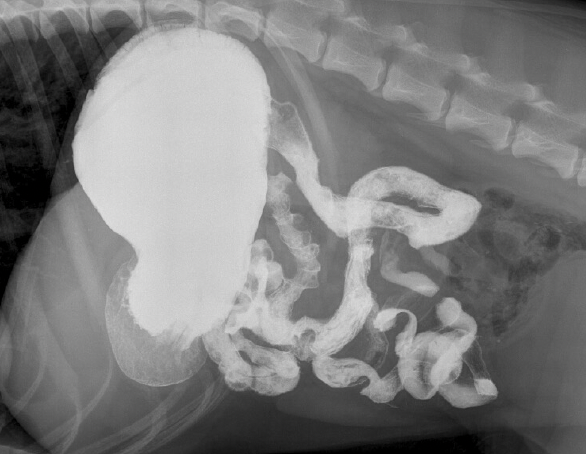

Cas 2: Charlot, un chien Labrador Retriever de 4 ans est présenté pour vomissements répétés depuis 2 jours

A. Obstruction mécanique secondaire à un CÉ

B. Gastroentérite

C. Pancréatite

D. Pyélonéphrite

A